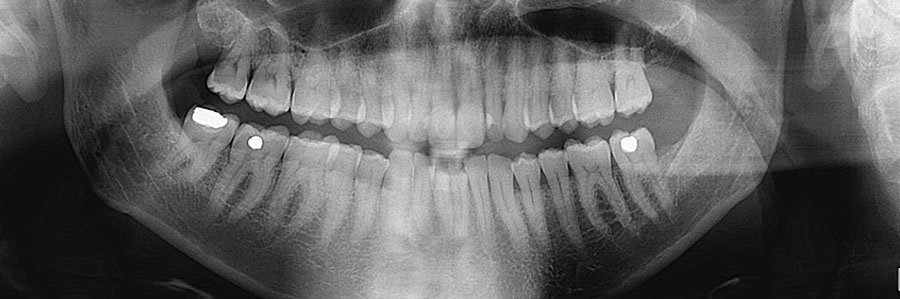

میزان دوز دریافت اشعه به هنگام رادیوگرافی دندان در حد میلیونیوم است. درحالی که قرار گرفتن درمعرض اشعه کیهانی نور خورشید به مدت 2 یا 3 ساعت که هر فرد دریافت می‌کند بیشتر از این میزان است. اشعه رادون در خاک، آب و بخصوص در هوا وجود دارد. هر فرد به میزان 6/3 میلی‌گرم در طول سال به‌طور میانگین اشعه دریافت می‌کند اما در هر صورت باید در زمان بارداری که مشکل دندان درد و عفونت‌های دندان اتفاق می‌افتد و نیاز به رادیو گرافی دندان وجود دارد. بهترین روش استفاده از شکم‌بند سربی است. با استفاده از آن رادیوگرافی انجام می‌شود و مشکل خاصی برای بیمار و جنین او بوجود نمی‌آید.

در دوره اول بارداری زمانی که جنین هنوز در رحم مادر کاملاً شکل نگرفته است، در این دوره ممکن است رادیوگرافی دندان موجب سقط جنین شود در برخی موارد که زن از باردار بودن خود آگاه نیست با انجام رادیوگرافی دندان احتمال سقط جنین او بالا می‌رود.

دوره دوم بارداری که دوران اندام‌ زایی جنین محسوب می‌شود. در این دوره ممکن است بیشترین آسیب را جنین از رادیوگرافی دریافت کند که عوارض آن روی جنین به صورت کند ذهنی و تأخیر در رشد اندام‌ها بروز پیدا می‌کند.

دوره سوم بارداری دوره رشد جنین است. خطر رادیوگرافی دندان کمتر از دوره اول و دوم است. رادیوگرافی دندان بهتر است در سه ماه سوم بارداری با استفاده از شکم بند سربی و به حالت ایستاده انجام شود که خطری برای جنین نداشته باشد. در ماه‌های اول بارداری بهتر است رادیوگرافی دندان انجام نشود. در صورت دندان درد و احساس ناراحتی در فرد برای از بین بردن عفونت می‌بایست به صورت سطحی آن را جراحی کرده و پانسمان را انجام داد و بعد از زایمان بقیه اعمال دندانپزشکی را به سهولت انجام داد.